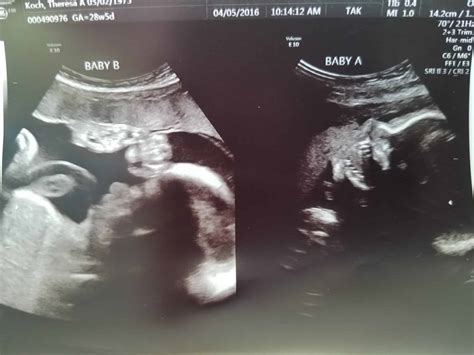

28 Weeks Sonography is a routine ultrasound scan conducted during the third trimester of pregnancy. This scan is often referred to as the "anomaly scan" or "mid-pregnancy scan" and is usually performed between 26 and 28 weeks of gestation. The primary goal of this ultrasound is to assess the baby's growth, development, and overall health. It also helps in identifying any potential complications that may require further monitoring or intervention.

During a 28 Weeks Sonography scan, the expectant mother will lie on an examination table with her abdomen exposed. A gel is applied to the abdomen to enhance the transmission of ultrasound waves. A transducer, a handheld device, is then moved over the abdomen to capture images of the baby. The procedure is painless and non-invasive, typically lasting between 20 to 30 minutes.

The ultrasound technician will measure various parameters, including:

• The baby's head circumference

• The baby's abdominal circumference

• The length of the baby's femur (thighbone)

• The amount of amniotic fluid

• The position of the placenta

These measurements help in estimating the baby's weight and assessing overall growth. The technician will also check for any structural abnormalities in the baby's organs, such as the heart, brain, kidneys, and spine.